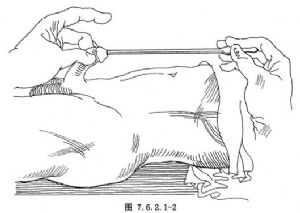

12.2 2.探子送入球部尿道

探子插入尿道外口後,仍保持其與病人腹壁呈平行狀態,繼續將探子向內插入,經過懸垂部尿道後,探子尖端滑入至球部尿道內(圖7.6.2.1-2)。